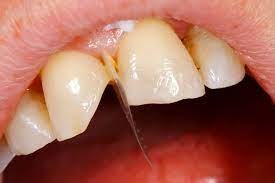

What Causes The Dark Line On My Gums?

You have seen smiles that you know have dental crowns in the front. You look at them and say to yourself that something is not natural. Many times, it is the dark rim of gum tissue that gives it away. The dark rim of gum tissue does not occur around natural teeth, only around teeth that have been covered with dental crowns.

The dark line is associated with an old porcelain dental crown. This style of dental crown is referred to as a porcelain fused-to-metal dental crown because it uses tooth-colored porcelain on the outside and it uses metal under the porcelain for strength. The dark line originates from the edge of the dental crowns where the porcelain and the metal meet at a knife-edge at the gum line. At the knife-edge, a very thin amount of the metal always shows. One of the illusionary techniques cosmetic dentists have used was to hide the thin dark line under the gum line. Over time, the gum tissue would recede and expose the dark line. In some patients the dark line would show through the gum and make it appear dark as well.

How Do You Get Rid of It?

The only way to eliminate the esthetic problem is to replace the dental crowns. When replacing just one single dental crown in the front, you should expect that it might take more than one try-in of the new dental crown before it is permanently cemented into place. Because your central incisors are the most prominent teeth in the mouth, matching them is the most difficult esthetic challenge. Only the best dental technicians are able to mimic one central incisor tooth next to another.

What Are Some of the Replacement Dental Crowns Like?

Some of the clever ways dentists and dental technicians have been able to mimic natural teeth is through the new advancements in dental materials. New all-tooth-colored ceramic dental crowns are the latest technological advancement cosmetic dentists have to recreate natural teeth. In comparison to porcelain fused-to-metal dental crowns, all-ceramic dental crowns do not contain any metal, thus no dark line can appear.